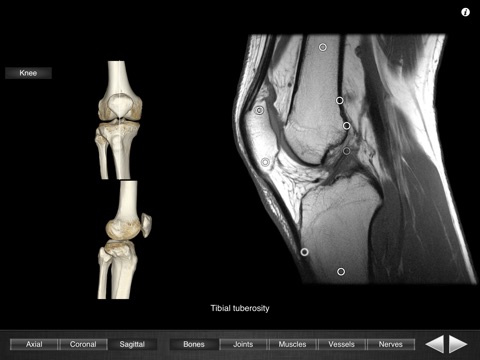

Monster Anatomy - Knee is the free version of Monster Anatomy - Lower limb, an interactive lower limb radiology atlas presented at the 2009 Radiological Society of North America annual meeting. It only contains knee images. The application was developed in the Medical Imaging Department of the University Hospital Center of Nancy, France, under the supervision of Professor Alain Blum. This application is designed for healthcare professionals (Radiologists, General Practitioners, Orthopedists, Surgeons, Physiotherapists among others) as well for students, as a reference and learning tool. It contains 82 contiguous knee MR slices (4-5 mm thickness) in the three anatomical planes. Features: - Intuitive navigation with multiple shortcuts. - Fluid display of images in the three anatomical planes. - 3D Image volume (VR) allows precise location of slice position. - Labels in accordance with the “Terminologia Anatomica" and current literature references. - The five different display modes available (bones, joints, muscles, blood vessels and nerves) facilitates label visualization. - High image quality with a zooming tool. Once the application is installed no network connection is necessary. You can download the full version on the AppStore : "Monster Anatomy - Lower limb" Dont hesitate to give some feedback on the application and to rate and comment on the AppStore! NB : Monster Anatomy - Knee is designed for trained healthcare professionals. This application is not intended as a substitute of patient/healthcare provider interaction or as a replacement of professional judgment.